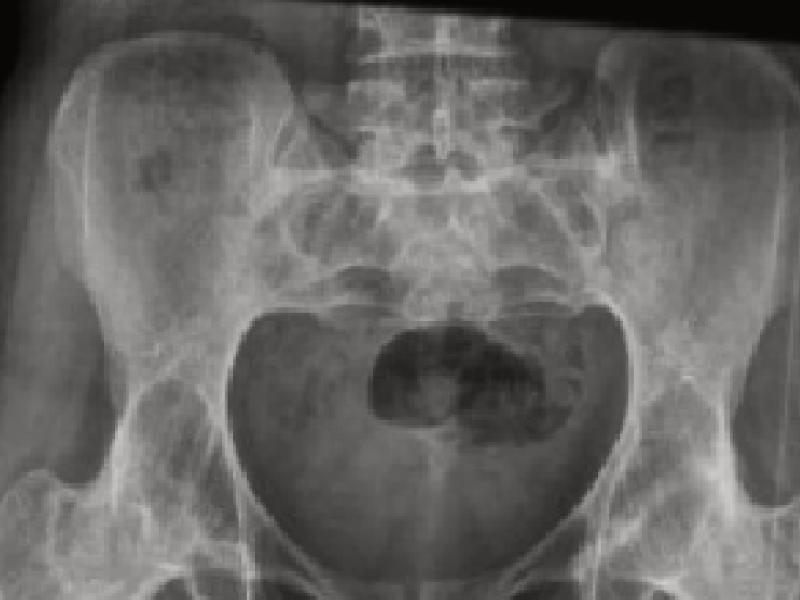

AS is not actually a standard disease. In other words, every person we diagnose immediately identifies with the deceased Suna Pekuysal and Ahmet Mete Işıkara. However, this behavior is actually a huge mistake. Each of our patients has a different course and the disease shows serious differences according to the person. In fact, the rheumatologist knows who will go bad and adjusts the treatment accordingly. The subject of this article is how our patients should live. While we are giving these recommendations, we have prepared a list based on medical references.